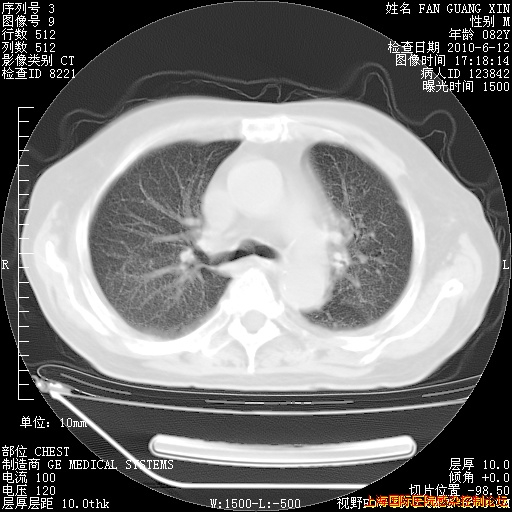

6月12日肺窗

今天复查CT

整整相隔30天的肺部CT好像有所好转啊。甲强龙减量第3天,需要观察体温。